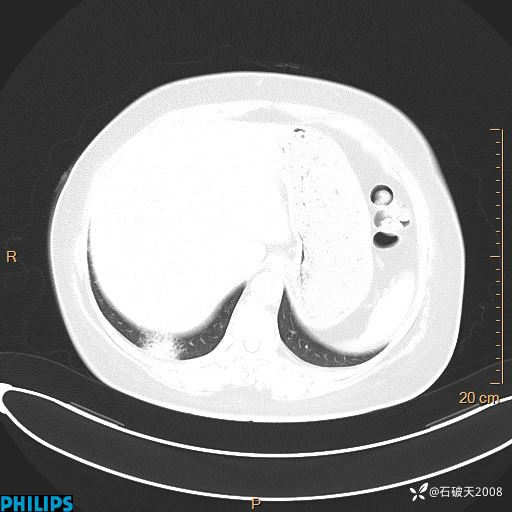

纵隔窗